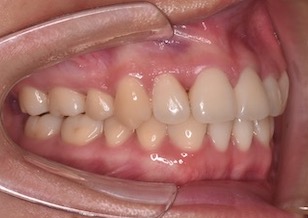

24歳女性の患者さんです。叢生(ガタガタの歯並び)を主訴に一般歯科からのご紹介で来院されました。上下顎歯列に重度の叢生を認め、左側の上下顎第1大臼歯がすれ違い咬合(交叉咬合)になっています。マルチブラケット装置を用いて便宜抜歯にて矯正治療を行いました。

上下顎歯列に重度の叢生(ガタガの歯並び)を認めます。下顎の右側側切歯は先天欠如を認めました。上顎右側側切歯は舌側に転位し反対咬合になっています。

また左側の上下顎第1大臼歯がすれ違い(交叉咬合)となっています。~すれ違い咬合の改善は難易度が高い治療となります。~